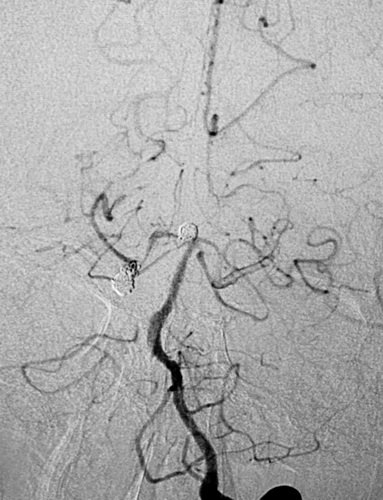

先微导管Echelon到位右侧大脑后动脉瘤,小心成篮,在保留大脑动脉通畅情况下尽可能地多栓塞动脉瘤体部与顶部,对瘤颈的栓塞不强求;分别为Presidio 3D 5mmX17cm,EV3 3D 3mmX6cm,3mmX4cm,2mmX4cm,在观察形态学弹簧圈对载瘤动脉无明显影响后实行解脱,最后造影见右侧大脑后动脉动脉瘤顶端不显影,近端于瘤颈处仍有部分显影。 之后再退至基底动脉瘤内,行部分栓塞,EV3 3D 4mmX8cm,2mmX4cm, 1.5mmX2cm,1.5mmX2cm,不用支架,是因为考虑病情较重,脑室较大,术后可能要行脑室外引流术,而支架应用则需用双抗会造成手术操作困难。后期拟再行补救支架手术。

左侧椎动脉2D造影示右侧大脑后、基底动脉顶端动脉瘤

在处基底动脉瘤术后正侧位像